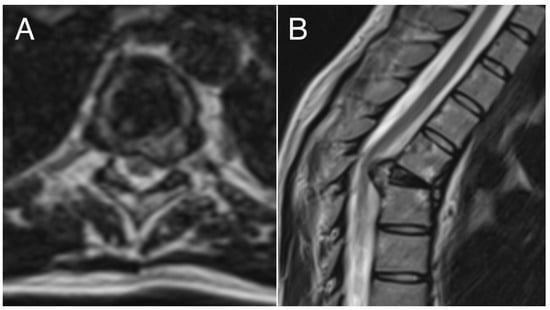

Figure 3. Pre-operative axial (A) and sagittal (B) MRI examination showing pathologic vertebra plana (T5) and spinal cord compression.